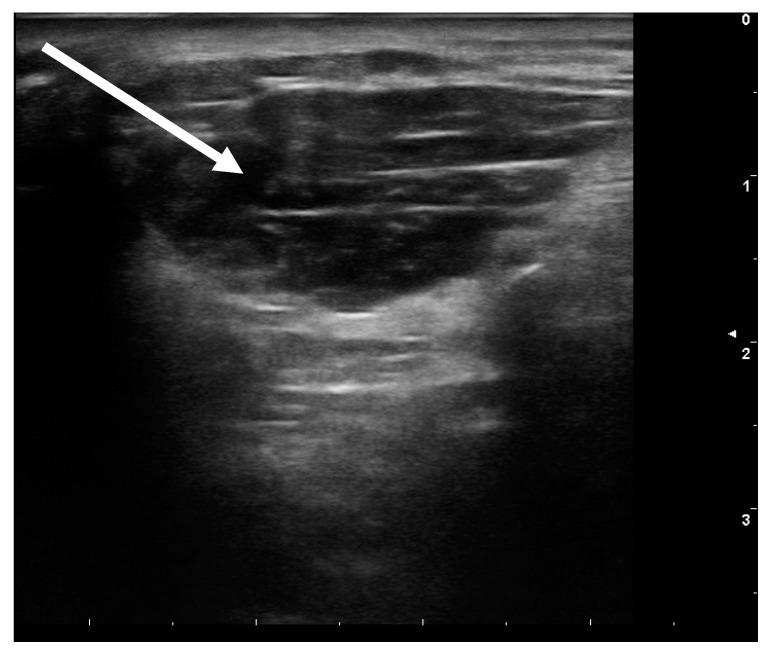

https://cdn.ncbi.nlm.nih.gov/pmc/blobs/89bb/7910947/bc36a2283d0e/toxins-13-00087-g001.jpg